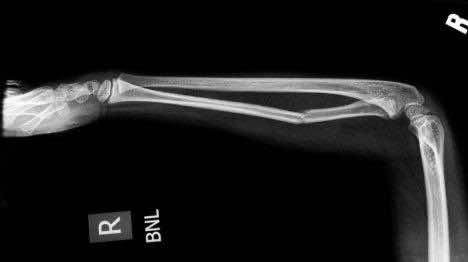

人体暴露在辐射下会发生什么(图片内容)